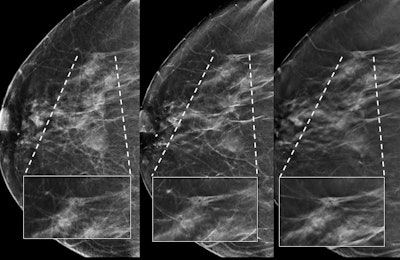

Architectural distortion in the left breast identified as invasive ductal carcinoma. Left to right: 2D mammography image, synthesized image, and DBT image. All images courtesy of Dr. Sara Romero Martín."Although initially we assumed that the difference between 2D mammography and tomosynthesis in terms of cancer detection rate would be greater than those obtained, we were surprised by the decrease in recall rate and the noninferiority of the synthesized image versus 2D mammography," Romero Martín told AuntMinnieEurope.com. "But the most relevant result was the superiority of the single reading of tomosynthesis plus synthesized, versus double reading of 2D mammography, with the important decrease in recall rate."